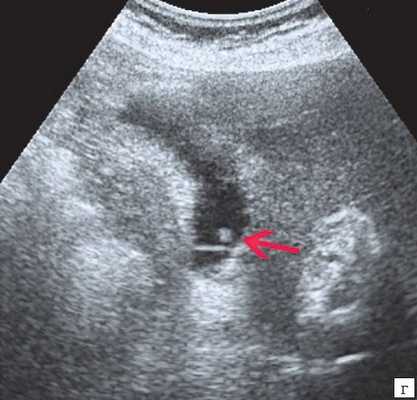

Клиническая картина желчнокаменной болезни многообразна [5-6, 10]. Условно выделяют хроническую болевую, хроническую рецидивирующую, диспептическую, стенокардитическую и ряд других клинических форм. Характерным ультразвуковым признаком конкремента в желчном пузыре является его акустическая тень. Такая тень возникает из-за высокой плотности камня по сравнению с мягкими тканями. Наличие или отсутствие тени помогает отличить камень от полипа желчного пузыря (рис. 4).

а) Одиночный конкремент желчного пузыря (подвижная гиперэхогенная структура, дающая четкую теневую дорожку).